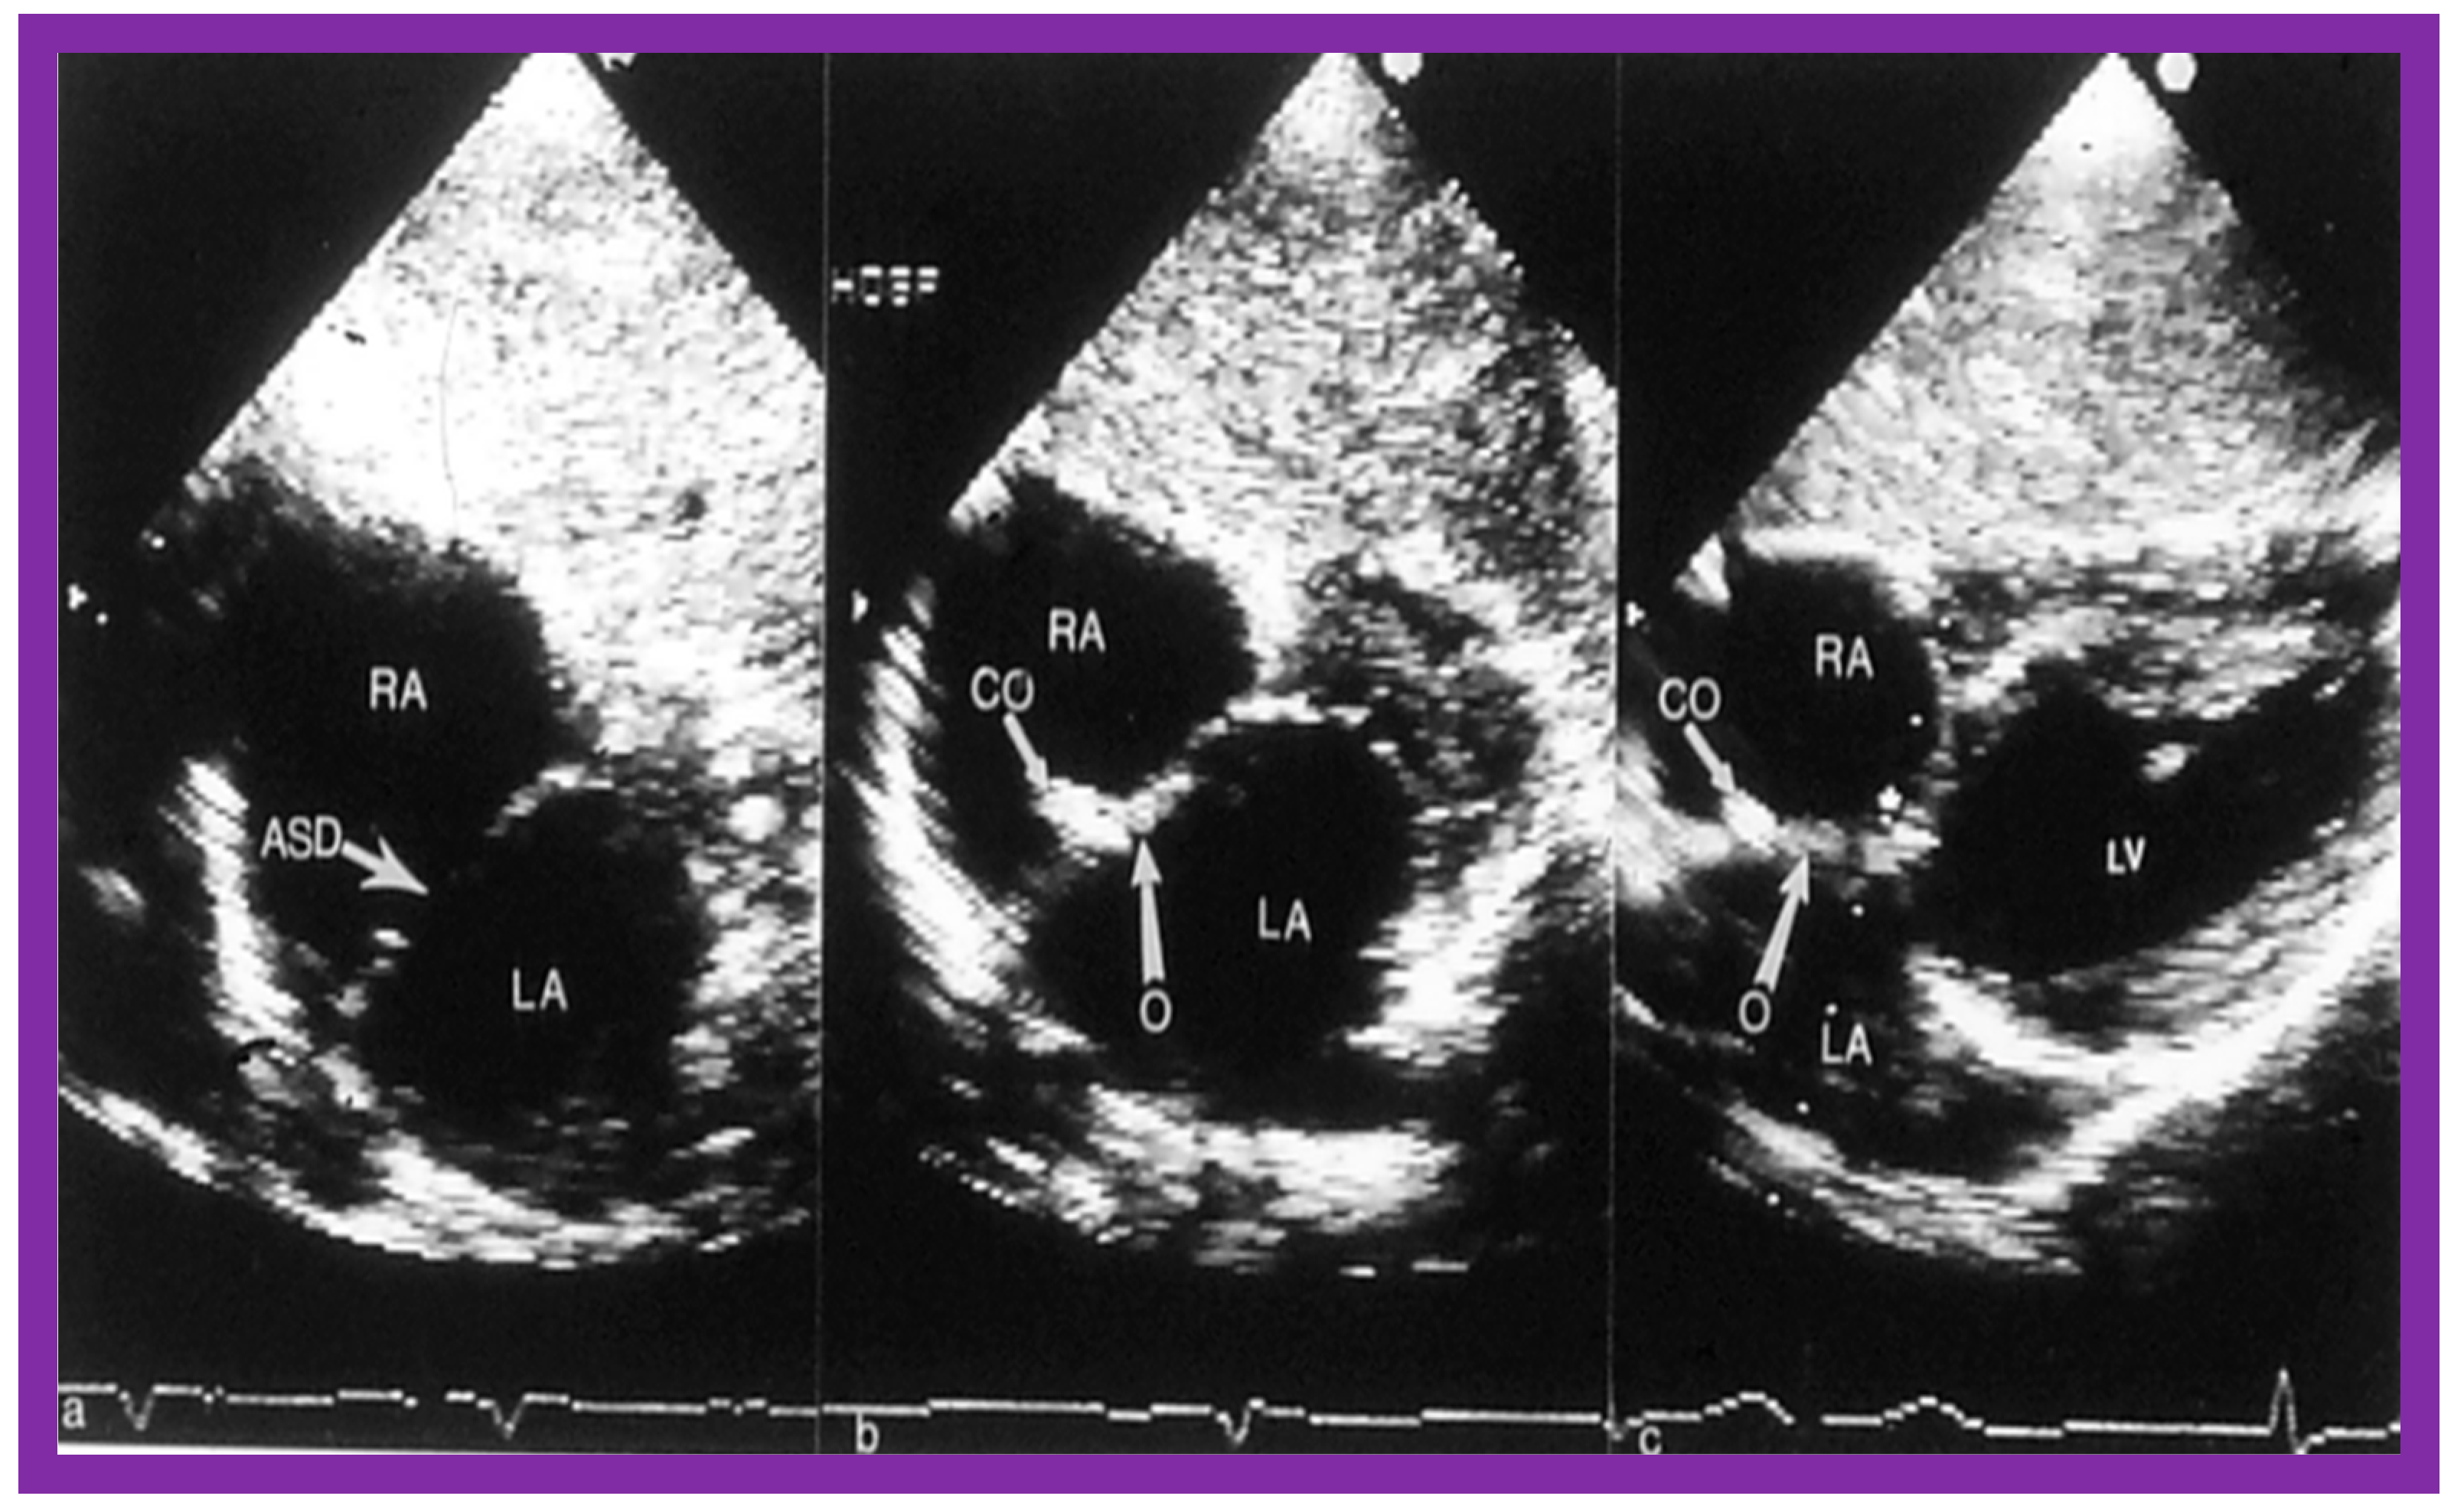

2. Diagnosis

7. Balloon Sizing

- Rao, P.; Langhough, R. Relationship of echocardiographic, shunt flow, and angiographic size to the stretched diameter of the atrial septal defect. Am. Heart J. 1991, 122, 505–508. [Google Scholar] [CrossRef]

- Rao, P.S.; Langhough, R.; Beekman, R.H.; Lloyd, T.R.; Sideris, E.B. Echocardiographic estimation of balloon-stretched diameter of secundum atrial septal defects for trans-catheter occlusion. Am. Heart J. 1992, 124, 172–175. [Google Scholar] [CrossRef][Green Version]